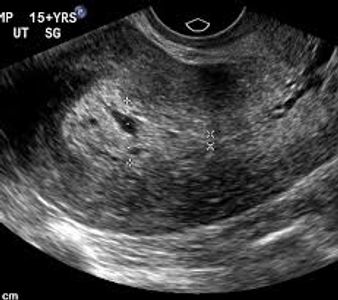

Most corpus luteum measure less than 5 cm. Sometimes we discover ovarian cysts which are larger than 5 cm, and which persist past 12 weeks. Ovarian cysts in pregnancy can be categorized as follows:

The need to worry, or the medical indication to intervene (to remove the cyst with surgery) is based on the combination of size, description, gestational age and symptoms. One end of the spectrum is the Absolute Need to remove a 12 cm cyst that is clearly causing pain at 15 weeks of pregnancy. The other end of the spectrum is warning Against removing a 4 cm simple cyst that is not causing any pain. Most patients have something in between.

Ovarian cysts can lead to a number of potential problems. In pregnancy the problems are more acute in the asymptomatic phase because the risk of premature delivery caused by (or associated with) surgical intervention Increases with gestational age after approximately 20 weeks. Also, the window for laparoscopic surgical management of ovarian cysts closes as the pregnancy continues past 20 weeks.